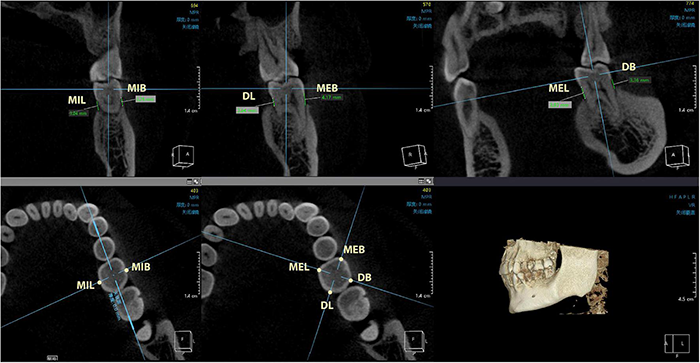

Twenty subjects were selected from each group (PD group or control group) to undergo cone beam computed tomography (CBCT) scan (KaVo 3D eXam i-CAT, Germany). The digital imaging and communication in medicine (DICOM) files were exported to the Invivo5 software (Anatomage, San Jose, CA, United States) for subsequent measurements. The distance from the CEJ to the ABC was measured at 6 sites (mesio-buccal, mid-buccal, distal-buccal, mesio-lingual, mid-lingual, and distal-lingual) (Figures 2, 3), and the average of the recordings was used as a measure of the bone loss for one tooth in millimeters. Alveolar bone loss was established when the distance between the CEJ and the alveolar bone crest was greater than 2 mm.

FIGURE 3